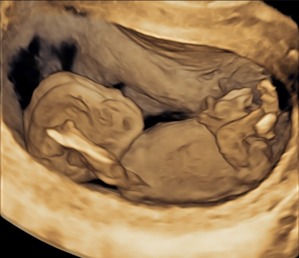

Nabízíme ultrazvuková vyšetření plodu sloužící k záchytu vrozených vývojových vad a chromozomálních poruch. Patří mezi ně prvotrimestrální kombinovaný screening v 11.-14. týdnu těhotenství a screening preeklampsie, kdy se kombinuje specializované ultrazvukové vyšetření plodu a odběr krve na biochemické markery. Dále ve druhém trimestru specializované ultrazvukové vyšetření plodu v 20.-22. týdnu včetně podrobného ultrazvukového vyšetření srdce plodu a konečně ultrazvukové vyšetření v 30. týdnu.